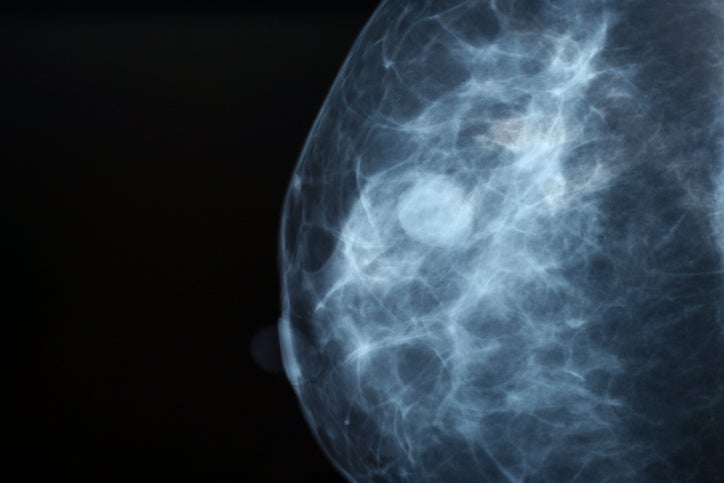

A breast fine needle aspiration (FNA) removes some fluid or cells from a breast lesion (a cyst, lump, sore or swelling) with a fine (thin) needle.The sample of fluid or cells (or tissue) is examined by a specialist doctor (a cytologist). An FNA can assist the doctor determine the nature or diagnosis of a lesion and, if necessary, to plan treatment.

If a lesion cannot be felt from the surface of the skin, ultrasound images or pictures may be used by the radiologist carrying out the FNA to guide the needle into the lesion.

Breast FNA is not 100% accurate. Cancer may not be definitely ruled out, even when there are no cancer cells found in the samples of tissue removed from your breast. The results must always be interpreted by the doctors caring for you in the context of their medical examination, findings of your breast imaging (mammogram and/or ultrasound) and the pathology results of the tissue (cells) or fluid sample. This is called the “triple test”.